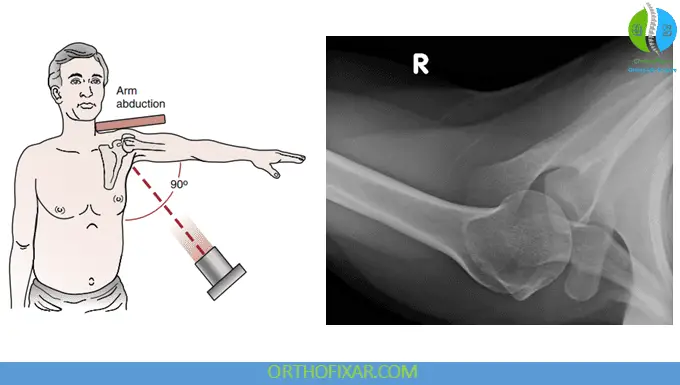

Axillary Lateral View

The axillary lateral view is used to visualize the relationship between the humeral head and glenoid, making it the gold standard for diagnosing anterior and posterior glenohumeral dislocations. This view requires the patient to abduct the arm 70° to 90°, which may limit its use in patients with acute injuries or significant pain.

Clinical Applications

This projection excels at demonstrating the coracohumeral distance and is particularly valuable for identifying avulsion fractures of the glenoid or Hill-Sachs lesions. The axillary view provides the best visualization of the acromioclavicular joint and allows assessment of calcifications in the subscapularis, infraspinatus, or teres minor muscles. Dynamic axillary views can be employed to evaluate horizontal instability of the acromioclavicular joint.